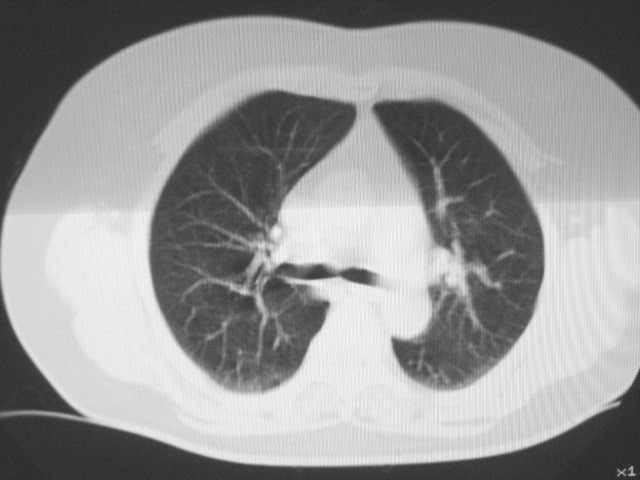

以下是引用清清楚楚在2007-8-28 7:13:00的发言:[br]右肺下叶可见斑片状高密度影,边缘模糊;右肺中叶内侧段及左肺舌段亦可见小斑片状模糊影。[br]考虑双肺感染,建议抗炎治疗后复查。

以下是引用天南地北在2007-8-27 23:49:00的发言:[br]右肺下叶可见斑片状高密度影,边缘模糊;右肺中叶内侧段及左肺舌段亦可见小斑片状模糊影。[br]考虑双肺感染,建议积极抗炎治疗后复查。

以下是引用天南地北在2007-8-27 23:49:00的发言:[br]右肺下叶可见斑片状高密度影,边缘模糊;右肺中叶内侧段及左肺舌段亦可见小斑片状模糊影。[br]考虑双肺感染,建议抗炎治疗后复查。

以下是引用难听在2007-8-28 13:17:00的发言:[br]右肺下叶背段支气管狭窄,是否可以考虑新生物伴阻塞性肺炎.请大家帮帮忙,这个病人是卫生局长的丈母娘.惹不起啊.